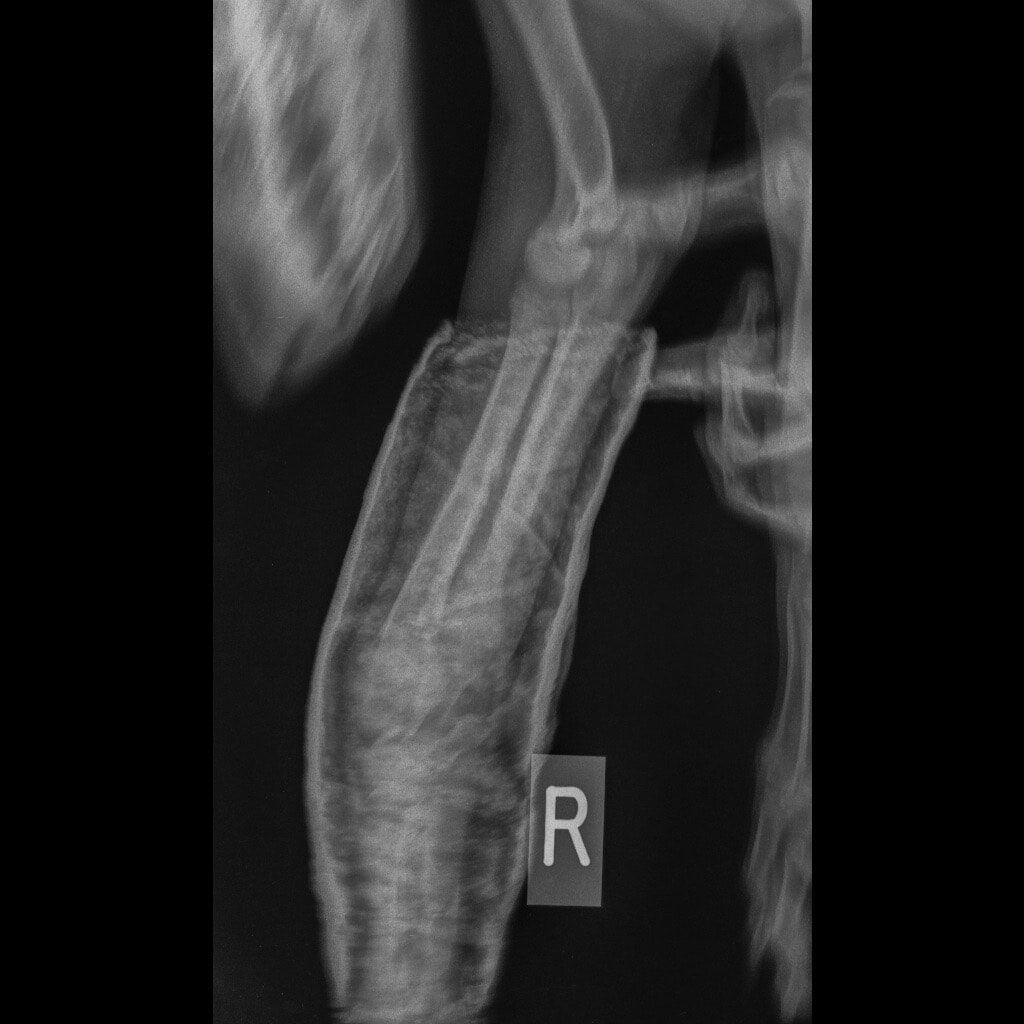

Ο Νικόλας βρέθηκε από εθελοντές και μεταφέρθηκε σε κτηνιατρείο. Δύο μπροστινά σπασμένα πόδια, πληγές, τσιμπούρια, ψύλλοι. Αυτή ήταν η κατάστασή του.

Η Maria Arkomani αναφέρει χαρακτηριστικά: «Δυστυχώς πολλοί ορθοπεδικοί έλειπαν και κάποιοι άλλοι δεν αναλάμβαναν το χειρουργείο του λόγω δυσκολίας και συγχρόνως επειδή είχαν περάσει μέρες από το σπάσιμο. Αμέσως πήγαμε στο κτηνιατρείο της Lena Kon για να δοθούν οι πρώτες βοήθειες από τον Νίκο Μαργαρίτη όπου τον ευχαριστούμε από καρδιάς. Βγήκαν ακτινογραφίες και έδειξαν τη ζημιά που είχε υποστεί αυτό το πλάσμα. Στο ένα πόδι μπήκε γύψος αλλά το άλλο ήθελε χειρουργείο. Στείλαμε σε πολλούς γιατρούς τις ακτινογραφίες αλλά οι απαντήσεις ήταν αρνητικές καθώς ήταν δύσκολο το χειρουργείο σε να κουτάβι με τέτοιο πρόβλημα. Ο μοναδικός γιατρός που μας απάντησε άμεσα και μπόρεσε να αναλάβει τον Νικόλα μας και να πάρει το ρίσκο του χειρουργείου είναι ο ορθοπεδικός Antonios Lionakis. Ένα χειρουργείο πάρα πολύ δύσκολο, με ρίσκο αλλά πρέπει να γίνει..»